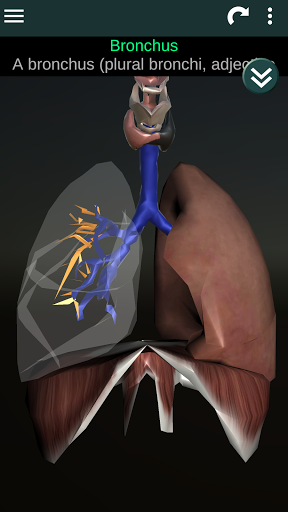

Показує 3D анатомічну модель основні органи людського тіла та опис кожного з них.

* Дихальна система, яка включає трахею, бронхи, легені та анімацію цієї системи.

* Описи кожного органу.